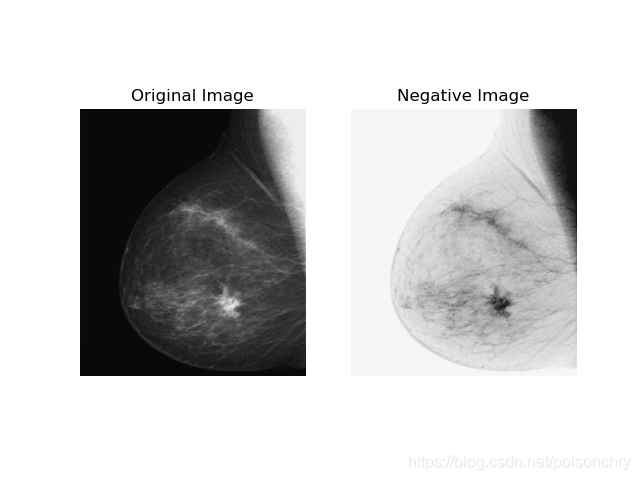

线性变换,又或者叫图像翻转,通常被应用于X光照片这类图像的处理。由于我们兴趣区域的数据多处于低密度区域,而这部分数据如果直接显示通常较难观察到(low intensity),例如X光来说,低密度的细节通常很难进行观察,而通过线性转换,则可以得到一些用肉眼不太容易注意到的细节。

比如这张对乳腺的X光照片,转换后的右侧图片中黑色斑块的位置,可能预示患者已经有了肿块,可能需要进一步的细致检查。